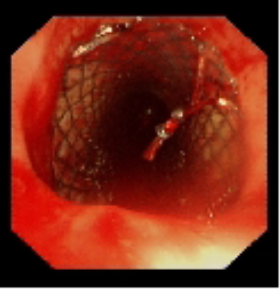

術中植入金屬覆膜支架